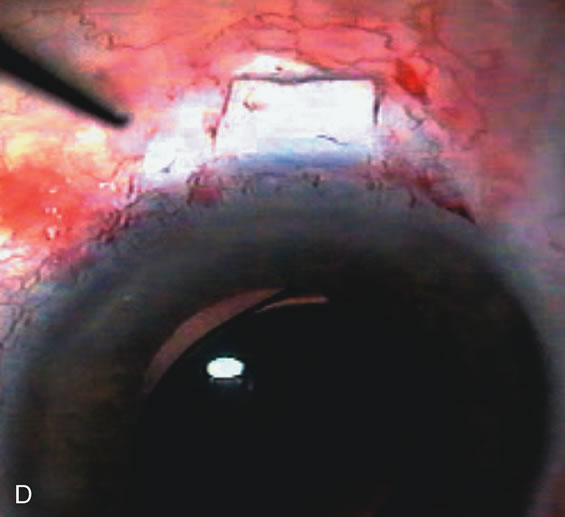

CASE 6: ANTICIPATED LENS EXTRACTION POST FAILED TRABECULECTOMY WITH ADVANCED DISC DAMAGE AND IOP OUTSIDE TARGET PRESSURE RANGE

The inflammation associated with lens extraction at any site usually causes complete failure of a marginal functioning bleb. In addition, pressure reduction by medical means is usually minimal in these recalcitrant cases, and combined surgery is indicated. In the past, these cases were approached with large-incision ECCE, clear corneal cataract incision, and bleb revision. Drawbacks included those mentioned earlier for large incision clear corneal cataract extraction, and bleb revision is often associated with conjunctival buttonholes, wound leaks, subconjunctival hematoma, destruction of friable sclera, and associated hypotony. With the advent of modern-day cataract surgery, a phacotrabeculectomy is often possible adjacent to the failed filter (Fig. 7). The ability to combine cataract extraction with implant and filtration surgery all through the same small incision has greatly improved outcomes for patients with marginal preoperative filters. There are several other viable options in this case. If the surgeon elects to remove the cataract through a temporal clear corneal incision, the bleb may be revised or a new adjacent filter fashioned. As mentioned earlier, revising a failed filter is technically challenging. If the surgeon believes it is not feasible to revise the filter or fashion a new one, a glaucoma drainage implant is a reasonable option combined with temporal lens extraction.172

Fig. 7. Phacotrabeculectomy adjacent to a failed filter in cataractous eye. The ability to combine small-incision cataract extraction with trabeculectomy all through the same incision adjacent to the failed filter allows the surgeon to work in a familiar superior area. Avoiding incisions into the existing bleb decreases conjunctival buttonholes, hypotony, operating room time, and subconjunctival bleeding. A. Appearance of failed bleb with exposure of superior temporal quadrant gained with a corneal traction suture. B. Prepare a limbus-based conjunctival flap and a scleral flap. C. This bleb is at high risk to fail again justifying the need for MMC, 0.2 mg/cc applied on a pledget for 4 minutes. D. Insert the keratome and perform phacotrabeculectomy in the usual fashion.